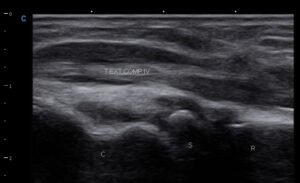

Tenosinovita, cu colectie in teaca tendonului